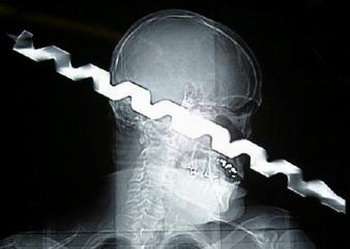

L’episodio recente che più ha fatto rumore è quello di un impiegato inglese di mezza età il cui cervello occupa nel cranio uno spazio assai inferiore al normale, un caso strombazzato ai quattro venti per via di una “lastra shock”, e quasi sempre associato al nome e cognome della persona coinvolta, che “non viene considerata un ritardato”. Ma si è parlato anche della radiografia di una donna cinese che metteva in evidenza degli aghi, o altri casi in cui emergevano pallottole nel cranio o persino matite.

Su Snopes , il sito antibufala per eccellenza, si trova nome e cognome di un operaio la cui radiografia ha fatto il giro del mondo, perché lo ritrae con la punta di un grosso trapano nel suo organismo. In quel caso, c’è da dire, l’operaio non solo è sopravvissuto ma ha anche partecipato di gusto come star del giorno a show televisivi negli Stati Uniti.